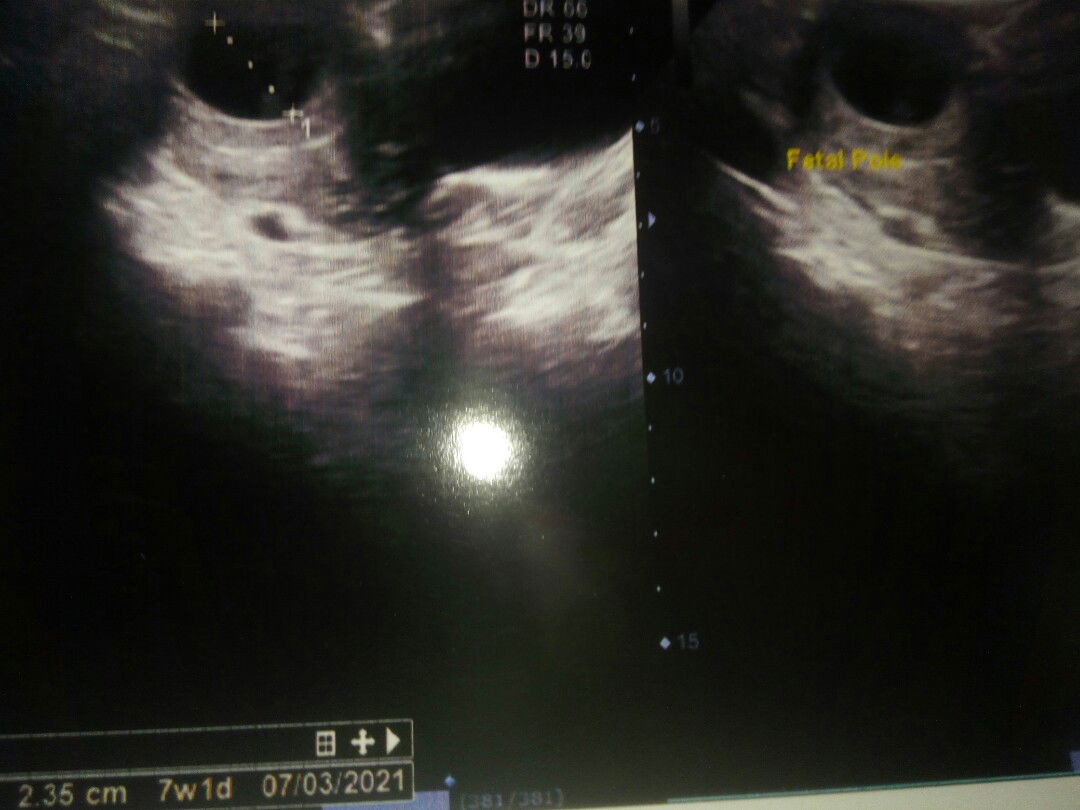

Hamil 7 week 1d maseh berbentuk kantong Bun apa wajar yah Bun???